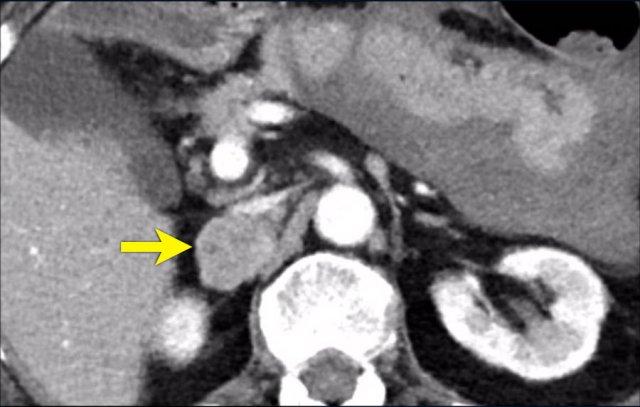

Trong 10% trường hợp, u tủy thượng thận có vôi hóa và thường có nhiều nang (mũi tên vàng).

Hình ảnh này cho thấy một trường hợp u tủy thượng thận khác với nhiều nang.

Các khối u lớn hơn có xu hướng xuất huyết và hoại tử, ngay cả khi chúng là lành tính.